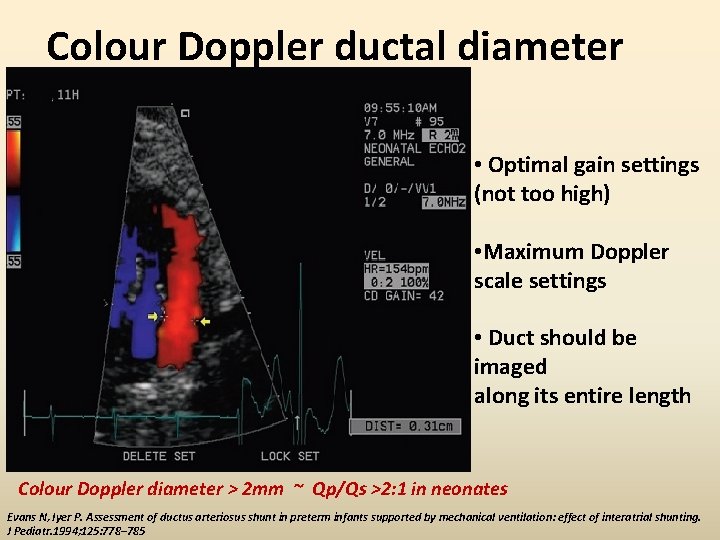

Colour Doppler ductal diameter • Optimal gain settings (not too high) • Maximum Doppler scale settings • Duct should be imaged along its entire length Colour Doppler diameter > 2 mm ~ Qp/Qs >2: 1 in neonates Evans N, Iyer P. Assessment of ductus arteriosus shunt in preterm infants supported by mechanical ventilation: effect of interatrial shunting. J Pediatr. 1994; 125: 778– 785